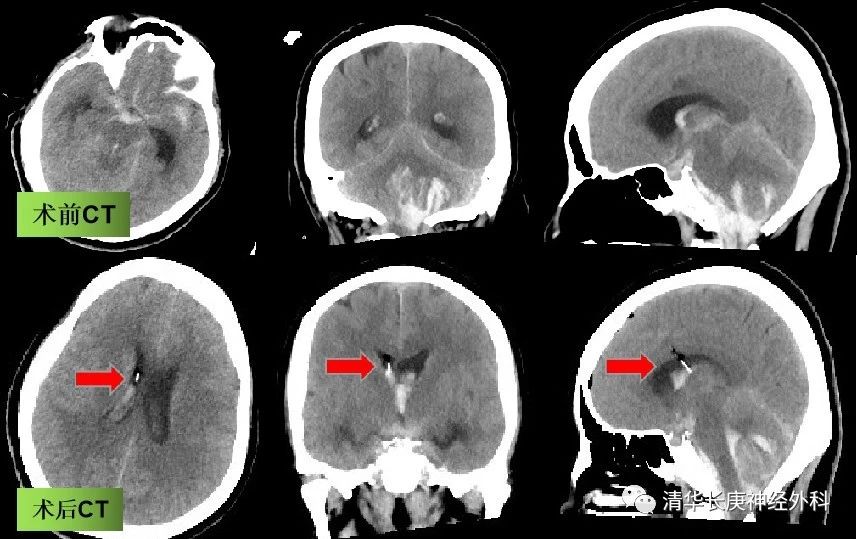

图7 手术前后CT,箭头示引流管,位置良好